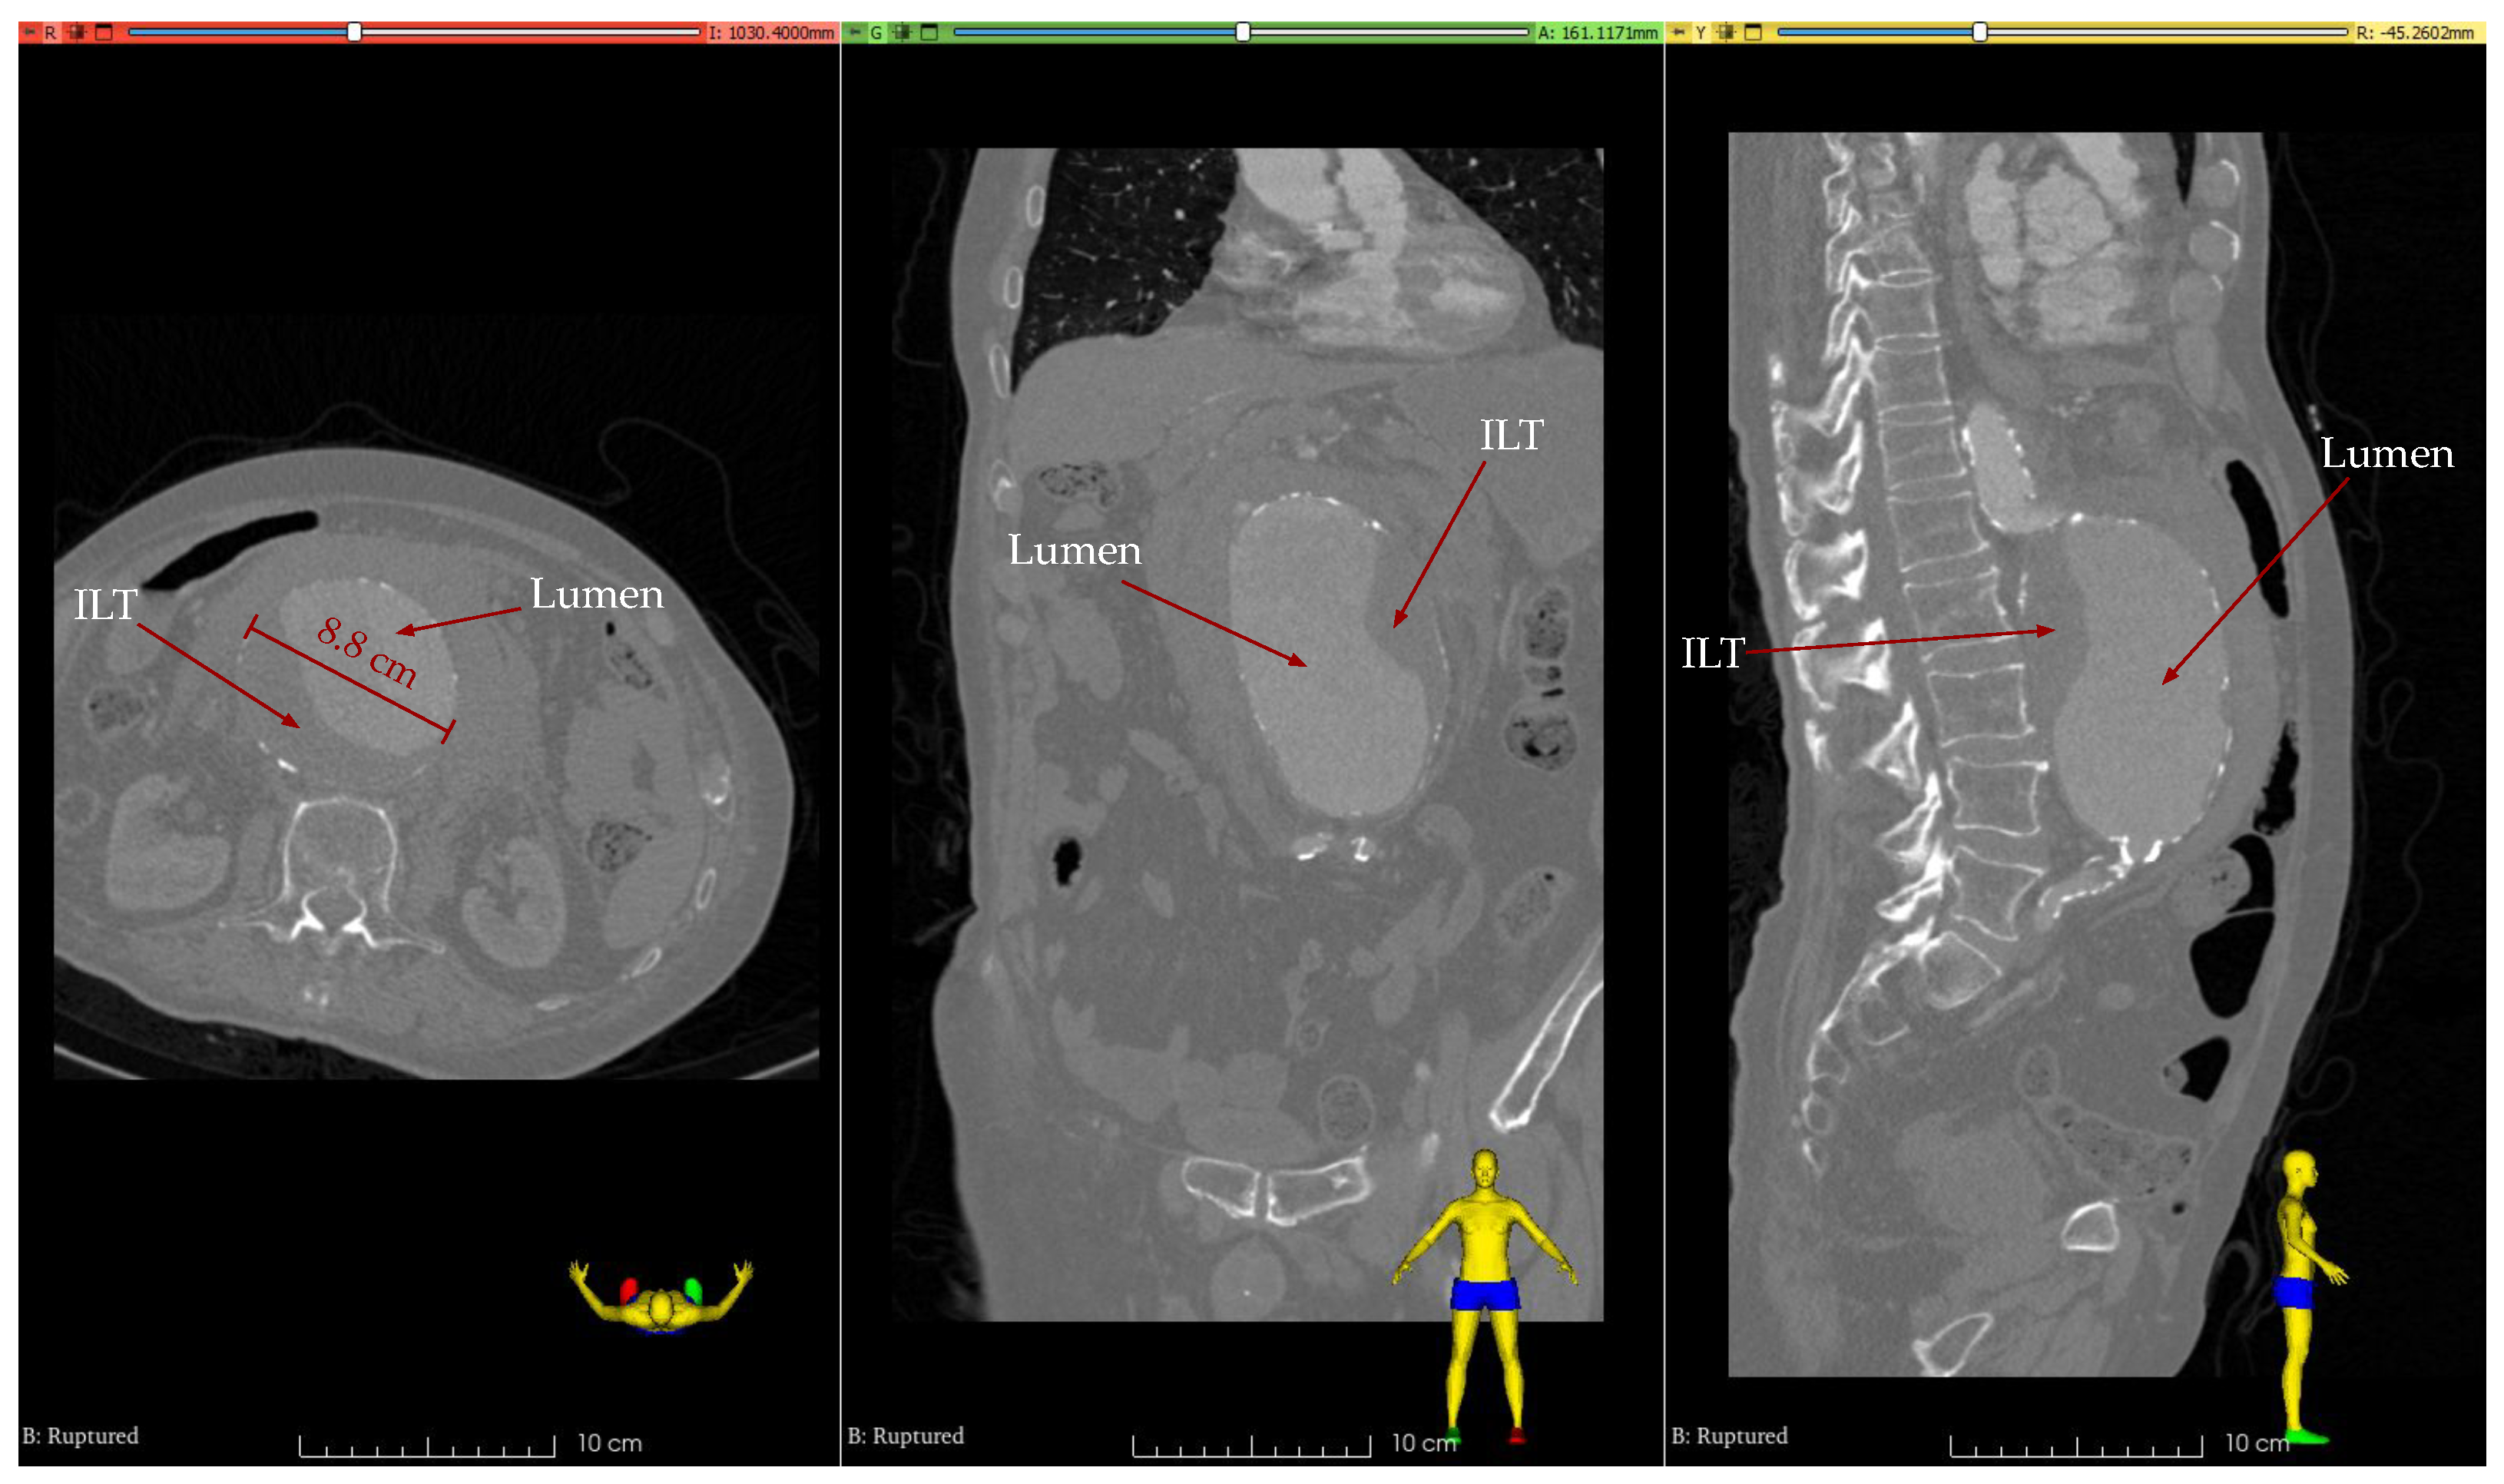

2.1. Clinical Case